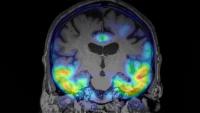

The Alzheimer’s Disease and PET (ADAPT) Imaging Lab focuses on PET imaging within Alzheimer’s disease and related dementias.

The Brickman Lab uses advanced neuroimaging techniques and fluidic biomarker methods to identify specific areas in the brain that are most vulnerable to the effects of aging.

Stern lab explores cognitive changes throughout aging and their neural basis, with a strong focus on state-of-the-art cognitive approaches and multi-modal imaging.